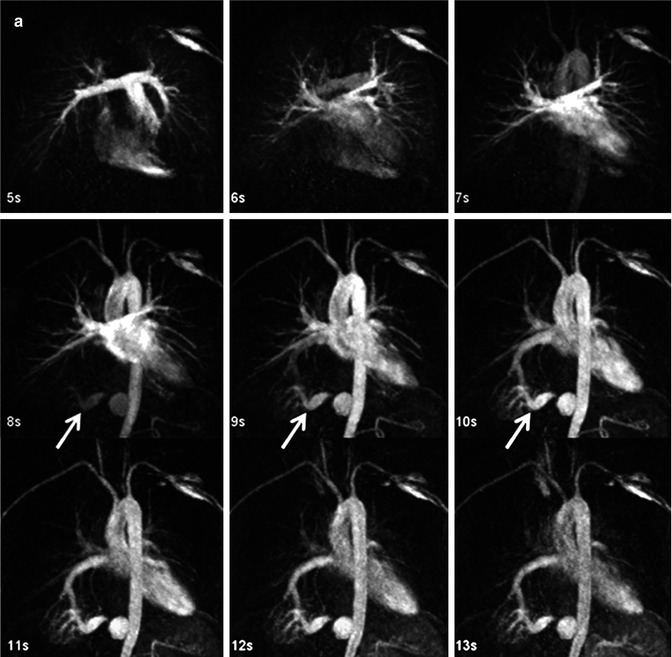

From www.ahajournals.org

Dynamic Resonance Angiography Provides Collateral Circulation Def Magnetic Resonance Angiography A magnetic resonance angiogram (mra) is a noninvasive test that allows your provider to see your blood vessels and blood. In magnetic resonance angiography (mra), a powerful magnetic field, radio frequency waves and a computer are used to evaluate blood. Magnetic resonance angiography (usually shortened to mr angiography or mra) is an alternative to conventional angiography and. Magnetic resonance angiography. Def Magnetic Resonance Angiography.